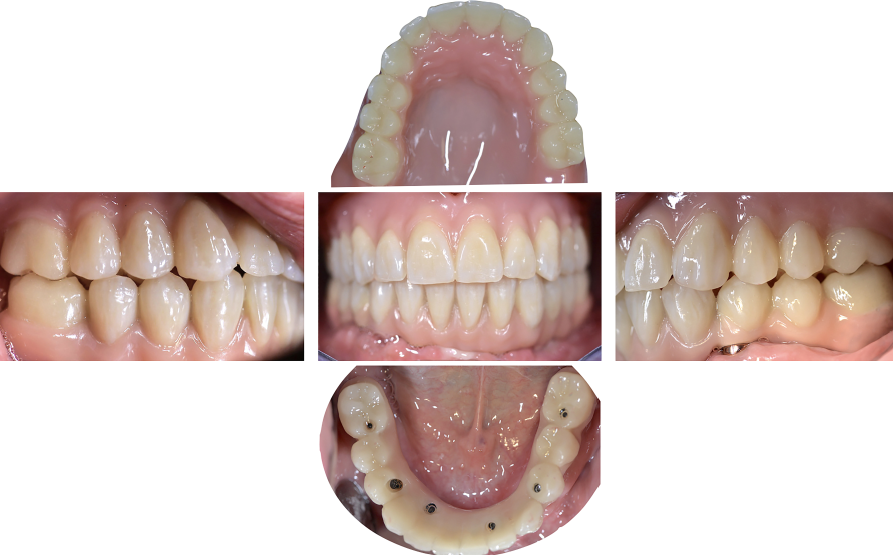

Un paziente maschio di 58 anni (Fig. 1), senza anamnesi medica rilevante, si presenta alla nostra attenzione richiedendo una riabilitazione protesica fissa su impianti alle due arcate. L’edentulia e l’atrofia ossea all’arcata superiore, come verosimile risultato di parodontite cronica dell’adulto, e la presenza di tre denti e due impianti con una prognosi parodontale infausta, sono evidenti all’esame clinico e nelle immagini radiologiche (Fig. 2), così com’è visibile l’incongruenza delle protesi rimovibili, con estetica compromessa e malocclusione in cross bite monolaterale (Fig. 3), con segni e sintomi disfunzionali.